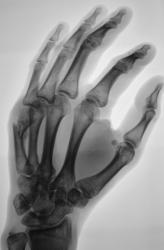

Катенёв Валенти... Дата публикации 02.12.2009, 22:30 Можно ли представленное рассматривать, как консолидированный перелом и выписывать пациента "к труду"? 1..VOPROS...JPG 2..VOPROS...JPG 3..VOPROS...JPG 4..VOPROS...JPG ВложениеРазмер 1..VOPROS...JPG71.9 КБ 2..VOPROS...JPG69.04 КБ 3..VOPROS...JPG77.01 КБ 4..VOPROS...JPG60.22 КБ Чт, 03/12/2009 - 14:39 #1 Глазков Игорь А... Не на сайте Был на сайте: 9 месяцев 2 недели назад Зарегистрирован: 19.12.2008 - 20:41 Публикации: 1597 определяется неправильно сросшийся субкапитальный перелом. Судить о возвращении к труду сложно, потому что , если труд физический, связанный с нагрузкой на кисть, то слабая костная мозоль может "дать трещину". Прийди к Себе Пт, 04/12/2009 - 18:35 #2 Vega Не на сайте Был на сайте: 3 месяцев 1 неделя назад Зарегистрирован: 22.01.2009 - 19:16 Публикации: 1087 Нет Пт, 04/12/2009 - 18:37 #3 Катенёв Валенти... Не на сайте Был на сайте: 7 лет 2 недели назад Зарегистрирован: 22.03.2008 - 22:15 Публикации: 54876 Спасибо Vega! Очень ждал, именно Вашего комментария. Еще раз большое спасибо.

определяется неправильно сросшийся субкапитальный перелом. Судить о возвращении к труду сложно, потому что , если труд физический, связанный с нагрузкой на кисть, то слабая костная мозоль может "дать трещину".